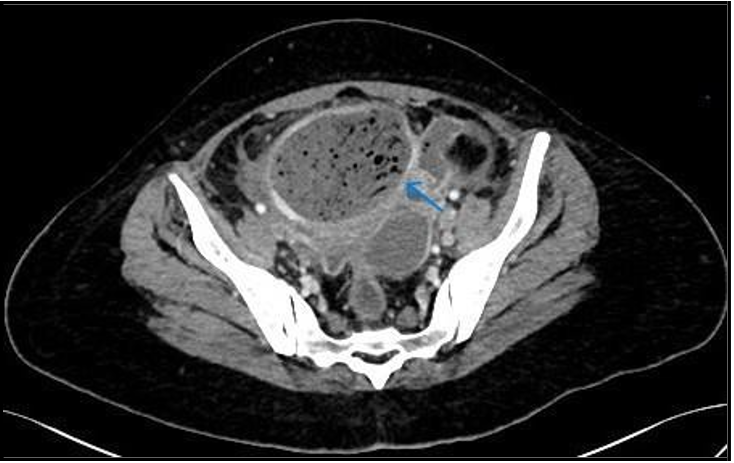

An Infrequent Case Of Pyomyoma After Uterine Artery Embolization

Corresponding Author: Namrah Khalid